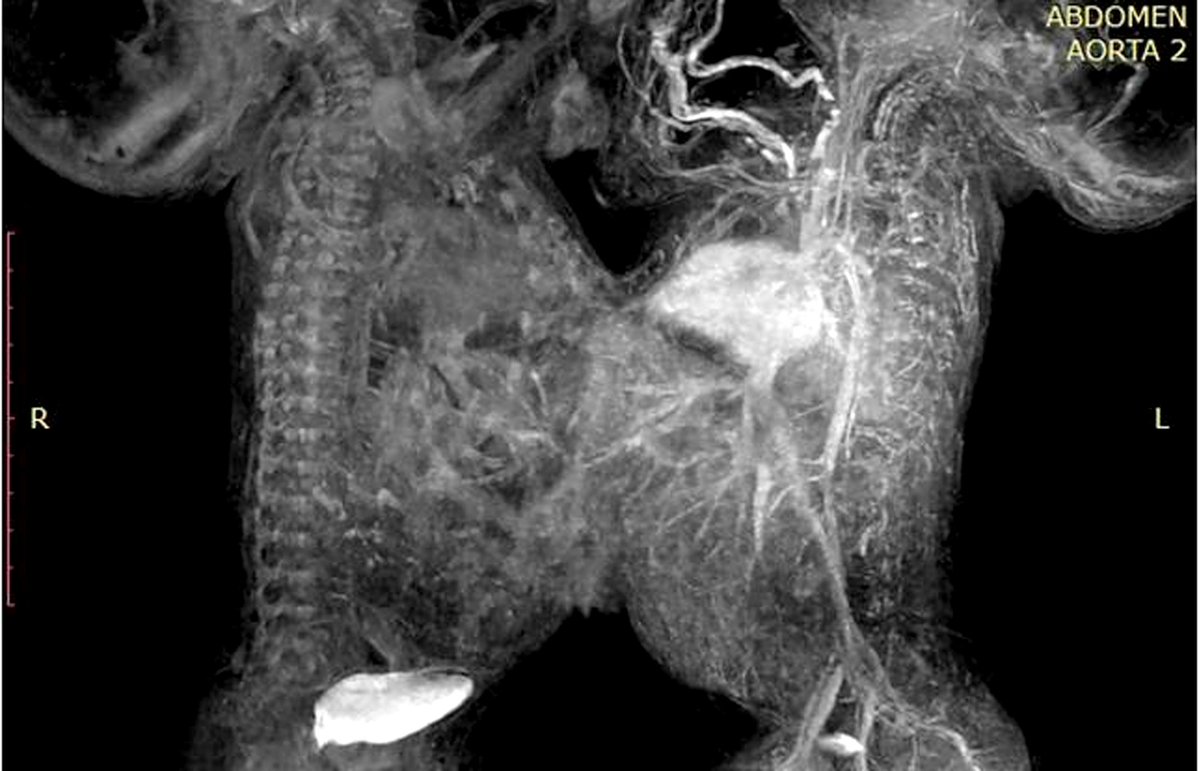

El IMSS informó que, tras diversos exámenes de tomografía, ecocardiograma y resonancia magnética, cuando los niños cumplieron 41 días de vida, fueron programados para la cirugía que los separaría.